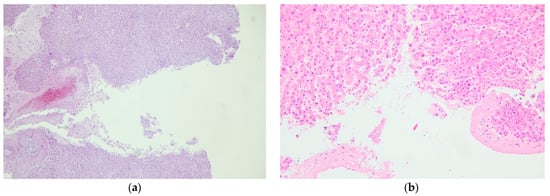

- Dye, D.W.; Peretti, F.J.; Kokes, C.P. Histologic Evidence of Repetitive Blunt Force Abdominal Trauma in Four Pediatric Fatalities. J. Forensic Sci. 2008, 53, 1430–1433. [Google Scholar] [CrossRef]

- Kohlmeier, R.E.; Dimaio, V.J.; Sharkey, F.; Rouse, E.A.; Reeves, K.E. The Timing of Histologic Changes in Liver Lacerations. Am. J. Forensic Med. Pathol. 2008, 29, 206–207. [Google Scholar] [CrossRef]